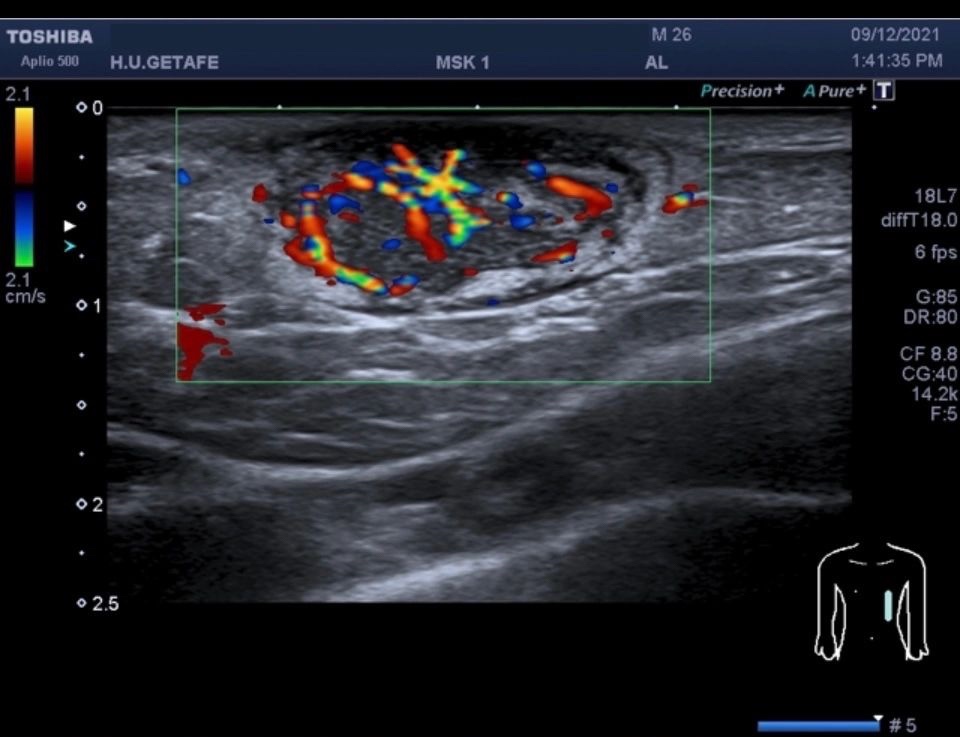

b. Doppler Color: Utiliza un mapa de colores para representar las velocidades relativas del flujo sanguíneo en tiempo real. Esto proporciona una visualización rápida y sencilla de áreas de flujo sanguíneo anormal.